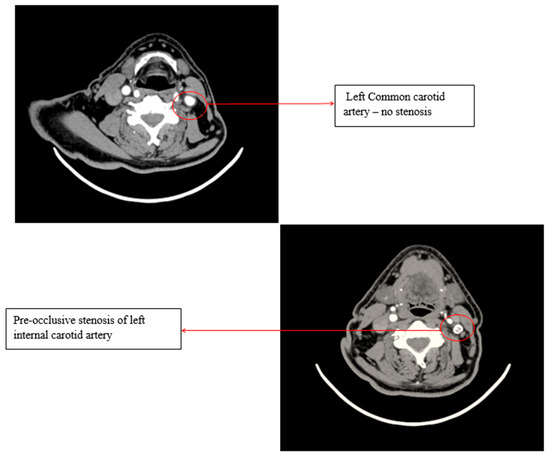

A Doppler ultrasound of the precerebral vessels, performed during the present admission, revealed a pre-occlusive stenosis of the left internal carotid artery, which was not present two years ago. This stenosis was confirmed by computed tomography angiography of the supra-aortic arteries (Figure 3).

Figure 3.

Computed tomography angiography (CTA) of the supra-aortic arteries.

Transient ischemic attacks appeared, despite correct anticoagulation and LDL-cholesterol levels under 50 mg/dL. The left internal carotid stenosis was most probably the cause. Aspirin was added to the treatment and the dose of atorvastatin was increased to a maximum of 80 mg, given the pleiotropic effects of statin in atherosclerosis.